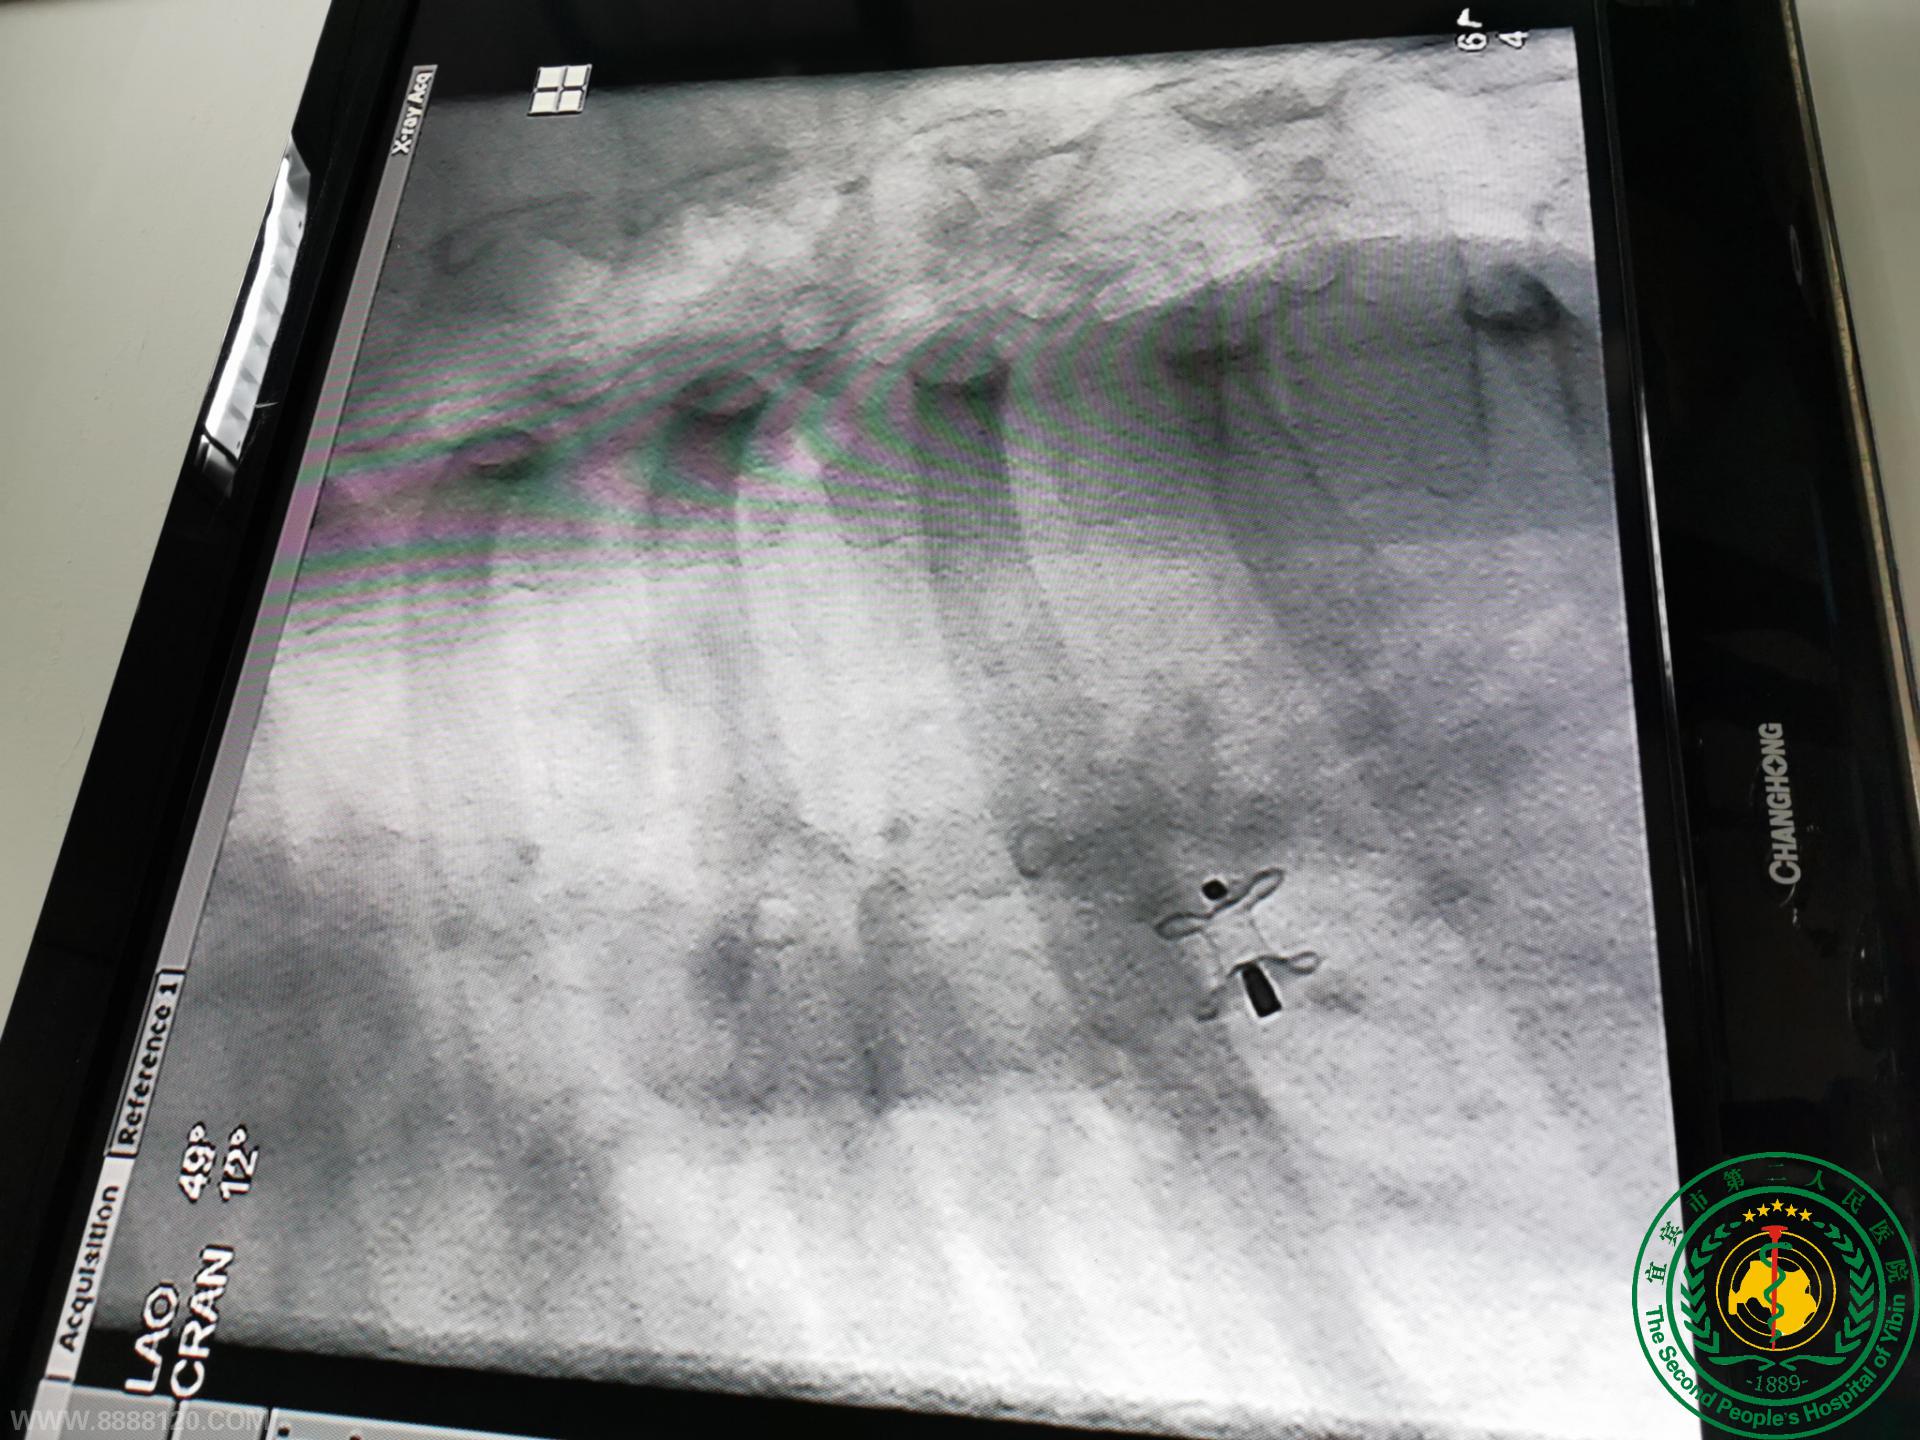

新年“心”行动,拯救“心”生命 ----关爱先心病儿童,宜宾市第二人民医院心内科一直在行动

新年“心”行动,拯救“心”生命 ----关爱先心病儿童,宜宾市第二人民医院心内科一直在行动23684